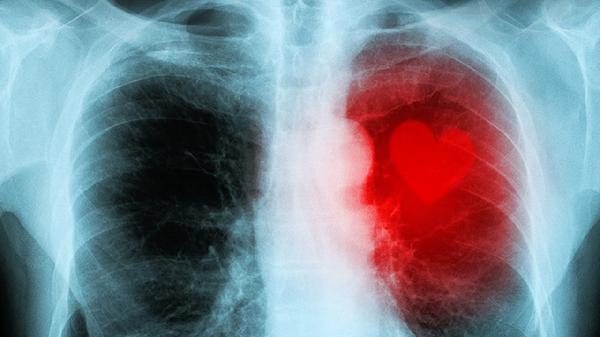

半年前睡觉就有异常,48岁女子查出肺癌,懊悔不已:当时没重视

48岁张女士半年前就发现睡觉时总是不对劲,却一直没当回事。直到最近咳嗽加重去医院检查,CT报告单上"肺占位性病变"几个字让她瞬间腿软。医生拿着片子直摇头:"要是半年前来,情况会好很多..."那些被我们忽视的睡眠异常,可能是身体发出的求.救信号。

3、体检项目不够精准

普通胸片对早期肺癌检出率不足15%。低剂量CT能发现0.5cm的结节,但很多人嫌麻烦不做。

1、每年一次低剂量CT

40岁以上人群,尤其吸烟者应该把这项检查纳入常规体检。辐射量仅为常规CT的1/5。